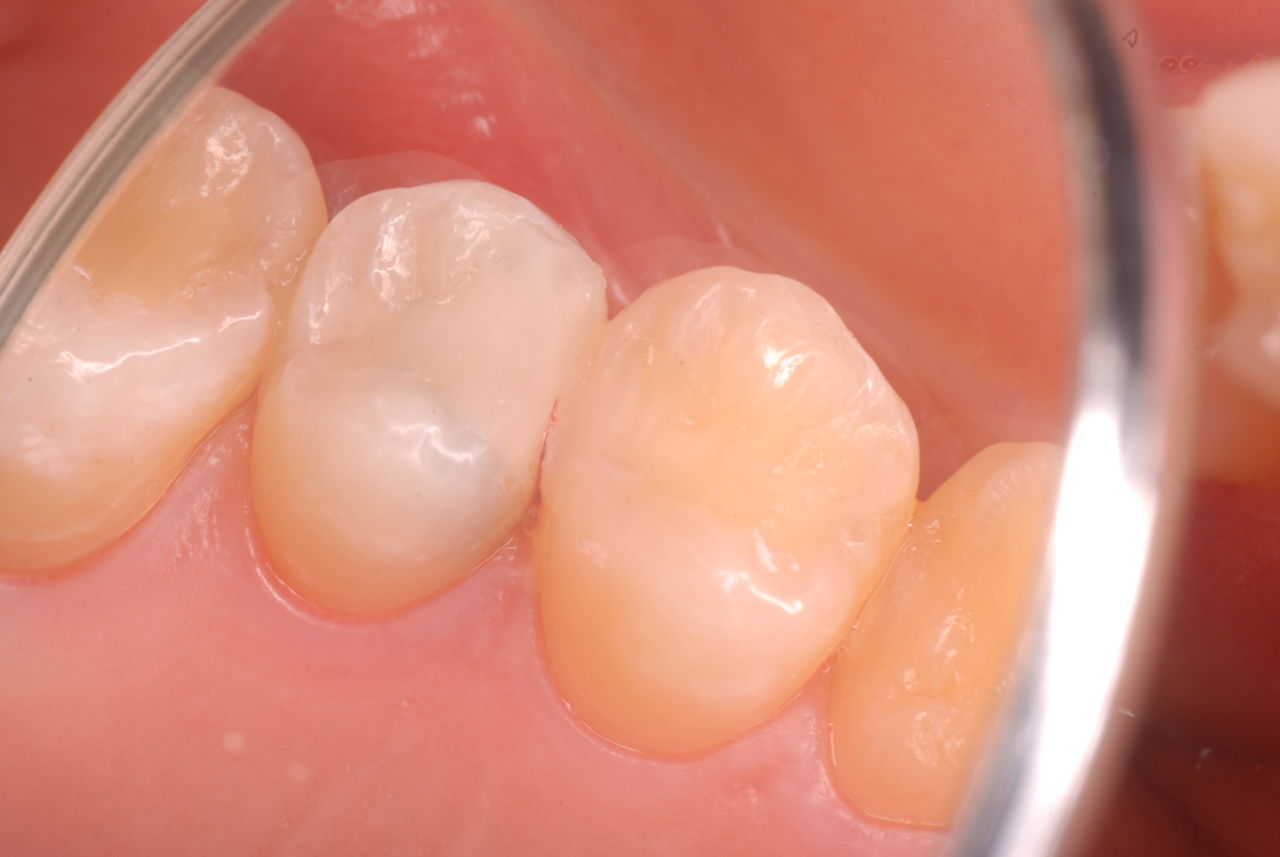

歯周病になっていましたが、少し色が黄色くなっているだけで比較的綺麗な歯の状態です。

平成24年一部欠けて来院

15年前と同じように詰めて終了。磨き方はまあまあでした。でも問題少ないでしょう。![ea7f9628-s[1]](https://livedoor.blogimg.jp/netdental/imgs/c/2/c2ef91be.jpg)